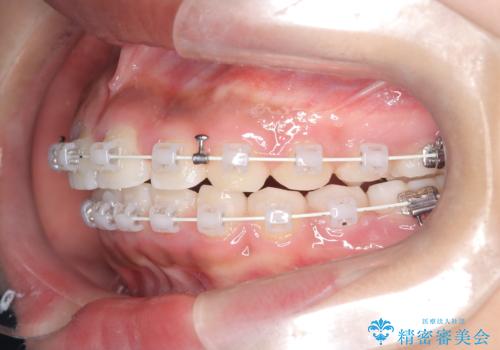

まず、上顎にリンガルアーチを装着し、歯列の幅を適正に維持しながら遠心移動をサポート。さらに、**TAD(矯正用アンカースクリュー)**を利用することで、奥歯を固定源とせずに前歯だけを後方へ移動させることが可能になりました。これにより、抜歯をせずに前歯の突出を抑え、バランスの取れた口元へと改善。治療後、患者様からは「抜歯せずに理想の仕上がりになり、大満足」とのお声をいただきました。